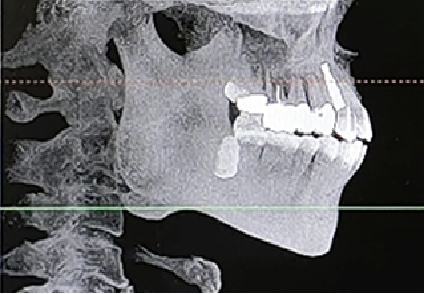

术前CBCT

21颊侧牙槽骨吸收至根尖,腭侧牙槽骨吸收至根尖1/3,根周可见低密度影。牙槽嵴宽度6.41mm。

局部反合、患牙长期牙周病变,骨质缺损,但软组织无明显缺失,为II类拔牙窝形态。

22冠状位CBCT情况

唇舌牙槽嵴宽度6.41mm,垂直骨缺失1/2,软组织无垂直向缺失。

术后即刻CBCT

术后CBCT

术前术后CBCT对比

唇侧过量植骨希望最终能够实现存量骨组织>2mm。

术后4.5个月CBCT

术后即刻与术后4.5个月CBCT对比

可见种植体唇侧顶端有一定骨粉吸收,但仍在预期范围内。